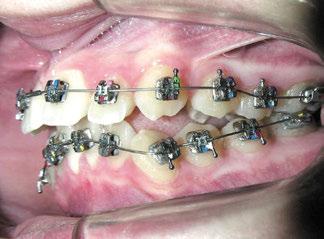

Figuras 1-3.

«La ortopedia dentofacial como tratamiento interceptivo en el inicio y en el pico de máximo crecimiento puberal ha sido muy satisfactoria en la estimulación del avance y/o crecimiento mandibular»

La niña de las figuras 1 a 3 presenta una leve asimetría facial con patrón braquifacial por tercio inferior disminuido y mentón desviado ligeramente hacia la derecha; los labios son competentes y en sonrisa apenas se exponen los incisivos. El perfil es excesivamente convexo,

La exploración intraoral (figuras 4 a 8) revela una Clase II molar y canina completa, líneas 1/2 dentarias superior 0,5 mm e inferior 1 mm ambas desviadas hacia la derecha, los incisivos superiores excesivamente protruidos y vestibulizados (seguramente debido a la interposición del labio inferior), resalte de 13 mm y sobremordida 2/3 de corona. La discrepancia oseodentaria

inferior es de -3,5 mm y la curva de Spee de 4 mm.

Con el cementado de los brackets de la técnica Universal Smile System

(USS), como se aprecia en las figuras 23 a 25, comienza la segunda fase de tratamiento. Esta duró tan solo 12 meses debido a que gran parte de las relaciones oclusales habían mejorado durante la etapa anterior. Los resultados finales del tratamiento se observan en las figuras 26 a 30 , con la corrección de la clase molar y canina, el resalte y la sobremordida, el centrado de las líneas 1/2 y la curva de Spee. La mejoría en la macro, mini y microestética facial se aprecia en las figuras 31 a 33 , a pesar de la evidente desviación del mentón hacia